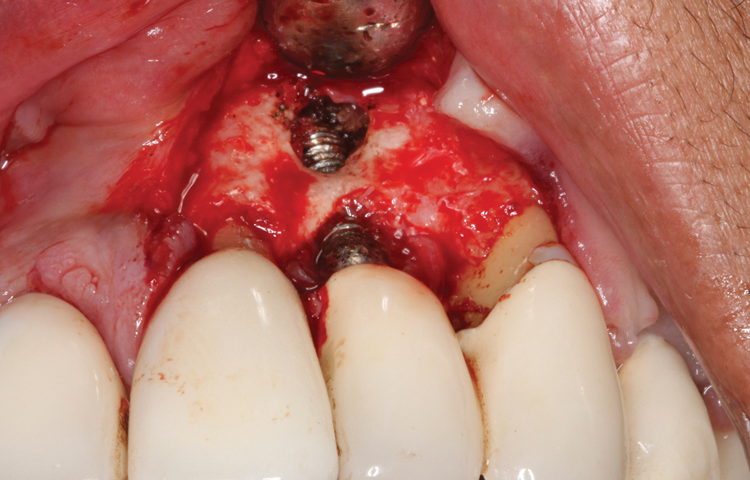

(5.) The physical granulation tissue was ablated, and the entire site was decontaminated, reducing the bacterial count.

Figure 5

(6.) View of the cleaned site ready to be repaired.

Figure 6

This is where the treatment became challenging. First, a curette was used to attempt to remove the granulation tissue from around the apex of the implant circumferentially. This was a difficult endeavor, especially on the palatal aspect of the site. Following curettage, an 810 nm diode laser (NV® PRO3, DenMat [alternatively: Picasso+, AMD Lasers; Gemini, Ultradent]) was used to treat the apical portion of the implant. After the laser tip was initiated using dark occlusal paper (Figure 4), it was used to debride the remaining necrotic tissue and decontaminate the entire site, reducing the bacterial count (Figure 5 and Figure 6).